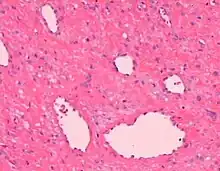

| Angiofibroma, Hematoxylin and eosin stain, magnification ×10. | |

AGF lesions share common macroscopic (i.e. gross) and microscopic appearances. Grossly, AGF lesions consist of multiple papules, one or more skin-colored to erythematous, dome-shaped nodules, or usually just a single tumor. Microscopically, they consist of spindle-shaped and stellate-shaped cells centered around dilated and thin-walled blood vessels in a background of coarse bundles of collagen (i.e. the main fibrous component of connective tissue).[2] Angiofibromas have been divided into different types but commonly a specific type was given multiple and very different names in different studies.[2]